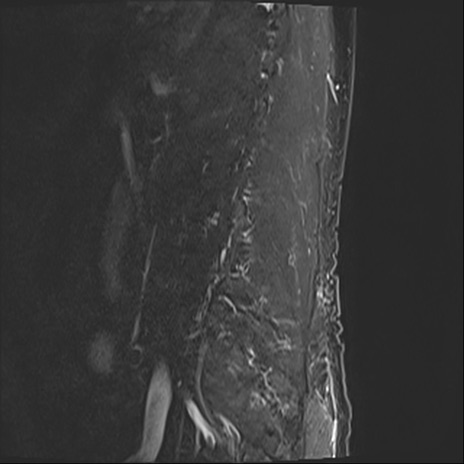

【整形】TIPS症例2 腰椎MRI STIR(矢状断像)

【症例】70歳代男性

【主訴】左下肢痛

【現病歴】2週間前くらいから腰痛、左下肢痛あり。左臀部から大腿、下腿外側のしびれが常時ある。歩行とともに同部位の痛みあり。

【身体所見】Lasegue70-/60+、Bragard-/±、PTR ±/±、ATR -/-、IP 5/5、TA 5/4、TS 5/5、EHL 右第1足趾なし/3、FHL 5/5、hypersthesia(-)、足背動脈触知良好

異常所見と診断は?